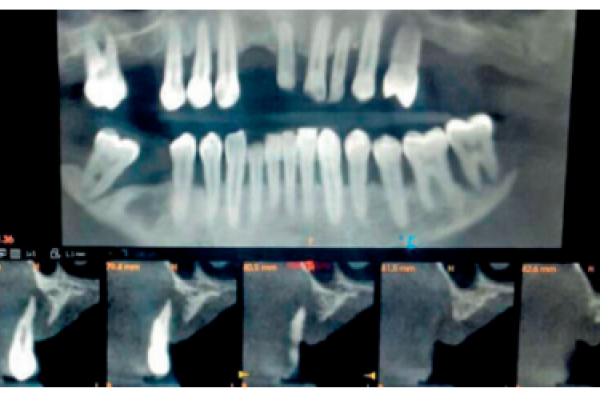

Comparación del Coeficiente de Estabilidad Implantaria ISQ entre implantes colocados en zona antral sobre hueso nativo frente a implantes colocados sobre hueso regenerado